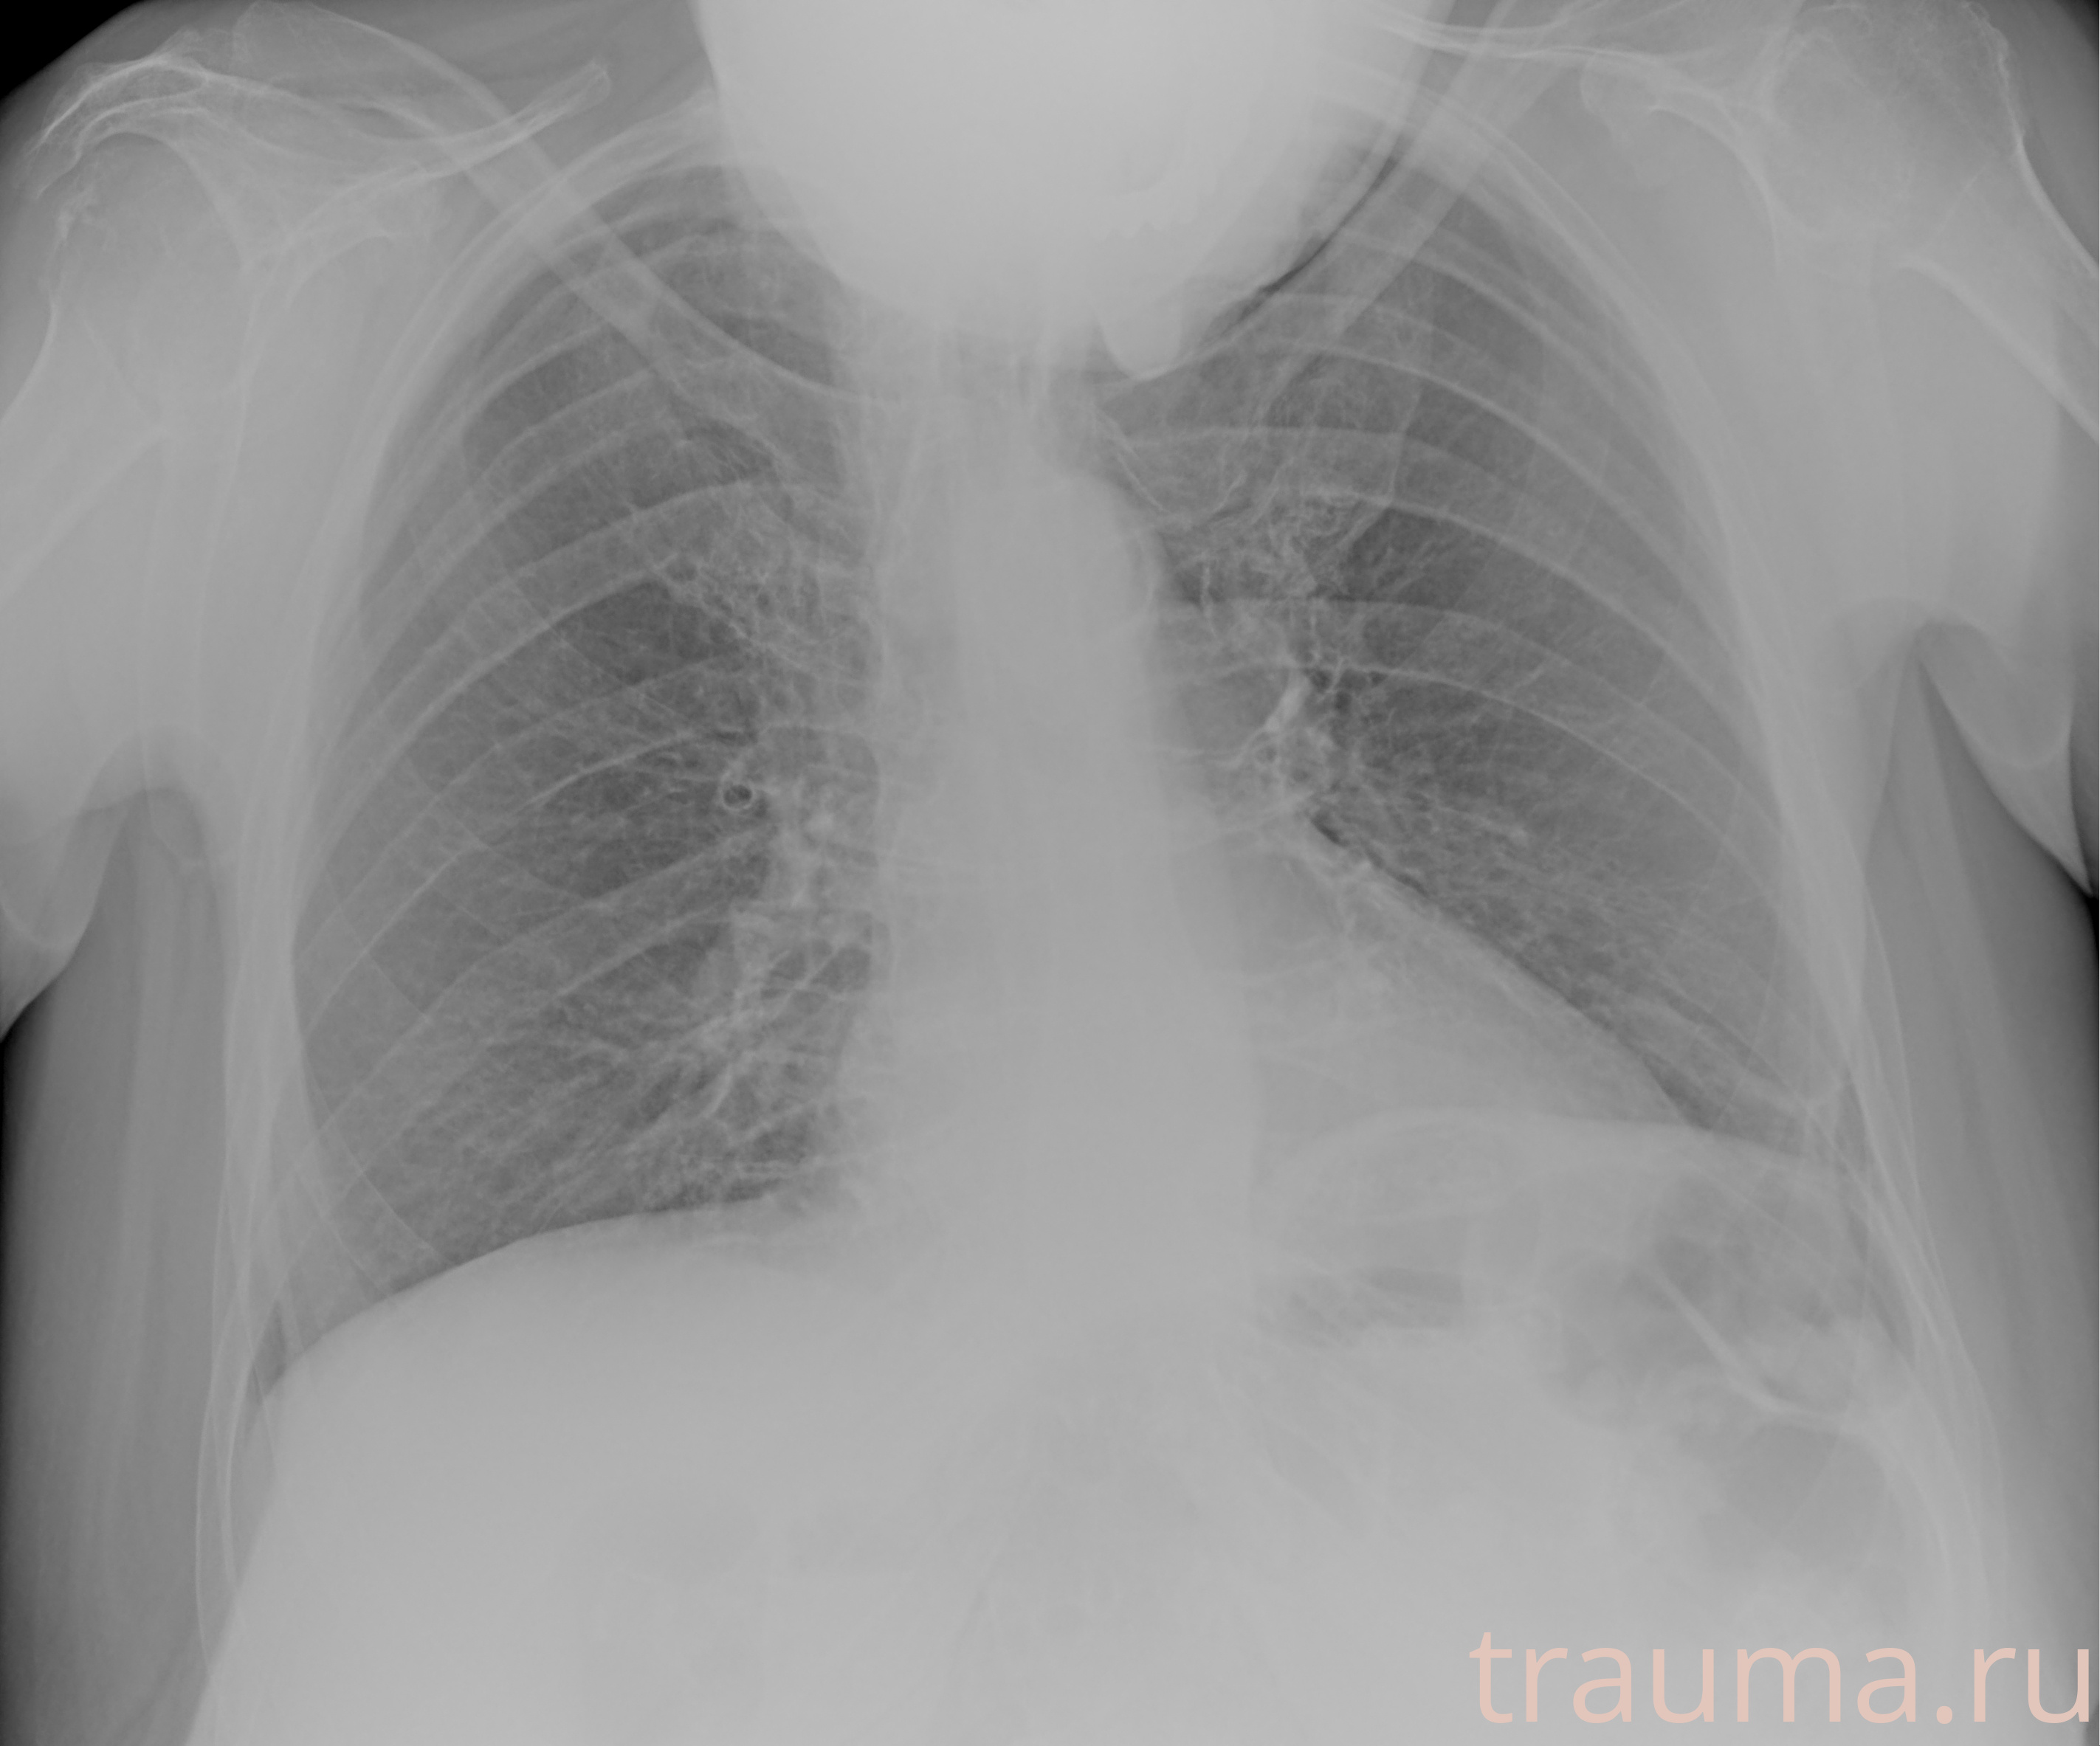

Рентгенограммы

Рентген на дому: по вашему адресу приезжает врач-рентгенолог, травматолог-ортопед с мобильным рентгеновским аппаратом, проводит диагностику травмы или заболевания, делает необходимые рентгенограммы, дает рекомендации по дальнейшему лечению. Получить качественные снимки в домашних условиях возможно благодаря уникальной методике, разработанной МосРентген Центром для института  Склифосовского